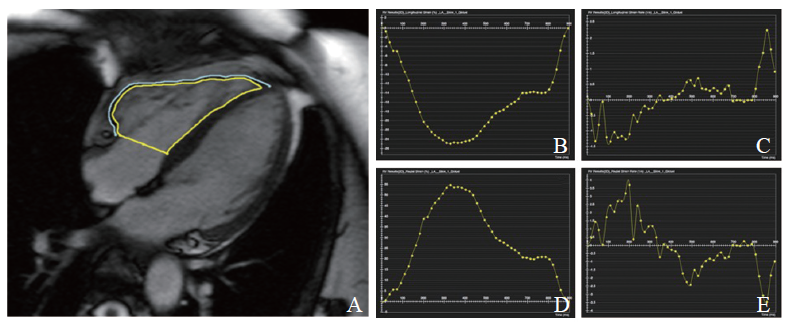

2.4 CVI42 Tissue tracking界面上进行右心室2D心肌应变分析

在四腔心电影舒张末期勾画右心室心内膜及游离壁的心外膜,Tissue tracking自动追踪分析右心室游离壁的应变,获得右心室纵向应变(RVLS)、右心室纵向收缩应变率(RVLSSR)、右心室径向应变(RVRS)、右心室径向应变率(RVRSSR),测量值均取绝对值(图1)。

图1 CVI42 Tissue tracking界面上进行右心室2D心肌应变分析

A:勾画右心室内膜及游离壁心外膜,计算得出右心室strain各值,并记录具体数值;B:RVLS;C:RVLSSR;D:RVRS;E:RVRSSR